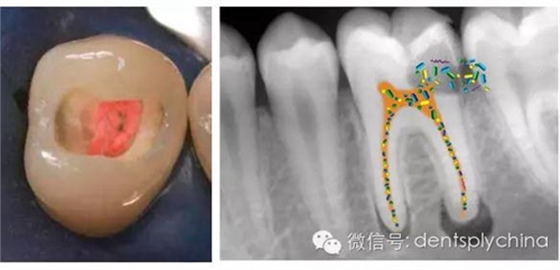

根管治療-消除根尖周感染

成功標準: 根尖周健康 = 沒有根尖周炎

根管治療成功率和嚴密的冠部封閉密切相關(guān)